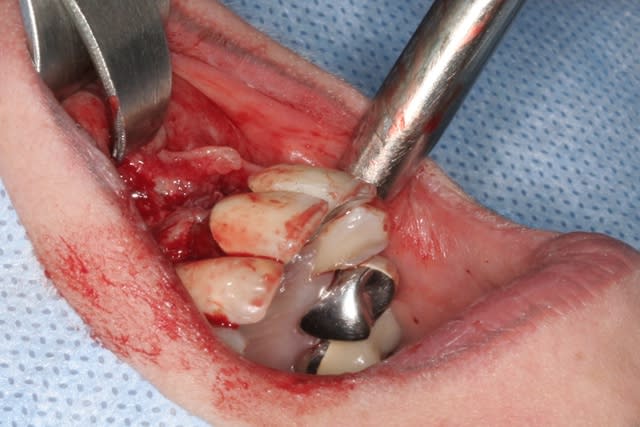

Voilà ce que l'on arrive à faire mais ce fut limite!

Interactive dx8dv8 - Eugenol